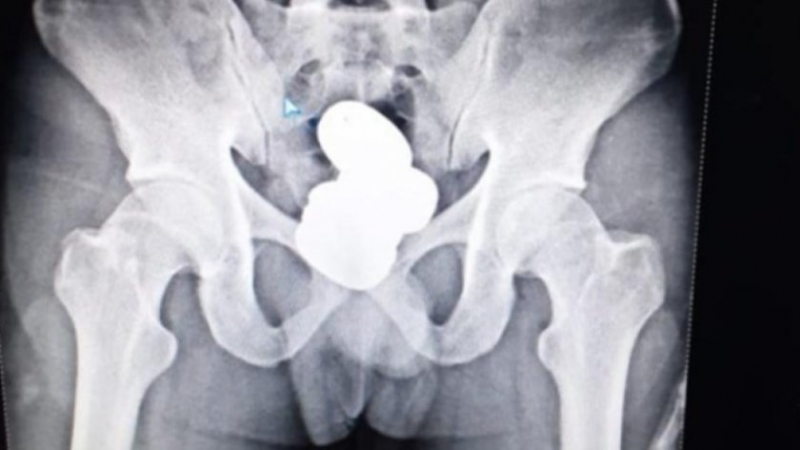

Контрабандист скрил почти един килограм златна паста в ректума си